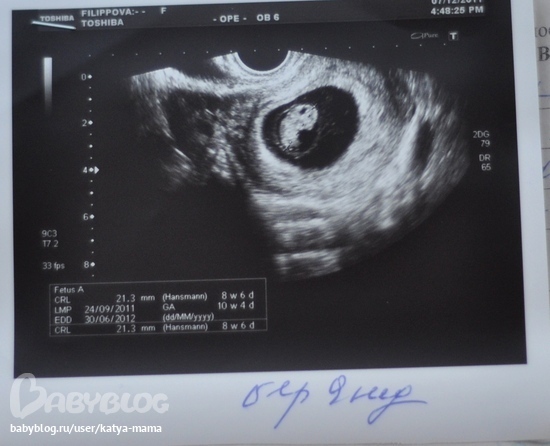

Совет! При проведении ультразвукового исследования могут быть измерены копчиково-теменные размеры плода, на 11 неделе беременности этот показатель составляет около 5 см. Но поскольку рост и развитие ребенка на этом этапе происходит стремительно, то уже через пару недель размеры вашего малыша увеличатся вдвое.

В первый раз рекомендуется проходить скрининг в период с 11 по 16 неделю. Причем врачи рекомендуют пройти это обследование, пока не началась 12 неделя беременности. Дело в том, что в это время хорошо видна воротниковая зона плода, а измерение этой части тела позволяет своевременно выявить наличие риска развития у плода синдрома Дауна.

Будущие мамы должны понимать, что при проведении УЗИ на 11 неделе беременности диагноз не ставят. Проведение скрининга позволяет определить степень риска. То есть, если будут получены результаты, не соответствующие норам, то будущей маме порекомендуют пройти дополнительные экспертные УЗИ и проконсультироваться у врача-генетика.

Женщина не способна пока ощущать движения плода, но при ультразвуковом обследовании они отчетливо видны.

На сроке одиннадцати недель проводится первый пренатальный скрининг, который направлен на определение пороков развития. Производится ультразвуковое и биохимическое исследование. Первый скрининг направлен не только на выявление пороков развития. Данное обследование позволяет узнать состояние хориона, рост и степень развития плода, точный срок беременности и другие подробности.

Примерно к одиннадцати неделям ваш ребенок официально становится плодом от эмбриона.У вашего ребенка развиваются отчетливые черты лица и гениталии, а сканирование за одиннадцать недель дает захватывающее представление о том, как ваш ребенок растет внутри вас. Сканирование, выполняемое на одиннадцатой неделе, также имеет важное медицинское значение для исключения любых аномалий, синдромов или пороков развития.

Цель 11-недельного ультразвукового исследования

Сканирование беременности в первом триместре всегда особенное, так как оно дает представление о развивающемся ребенке. Сканирование на 11-й неделе дает вам возможность впервые увидеть, как выглядит ваш ребенок.Это также самая ранняя стадия, на которой врач может обнаружить у ребенка определенные аномалии. У сканирования на 11-й неделе много разных целей. Вот несколько причин, по которым нельзя пропустить 11-недельное сканирование.

- Гестационный возраст ребенка проверяется по росту плода.

УЗИ в первом триместре на одиннадцатой неделе обычно представляет собой простую процедуру, которая занимает около нескольких минут.Опытный сонограф довольно легко измеряет прозрачность затылочной части. Они также проверяют другие жизненно важные параметры роста, такие как длина темени и крестца, диаметр гестационного мешка, положение и размер плаценты и т. Д. Положение плода может замедлить время, необходимое для сканирования. Иногда ребенок может быть повернут набок или свернут клубочком, что затрудняет измерение ткани ниже шеи. Обычно сонографист предлагает повторить сканирование через некоторое время, пока не будет установлено правильное положение плода.